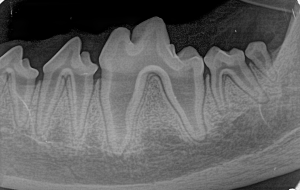

Canine Full Mouth Radiograph Example